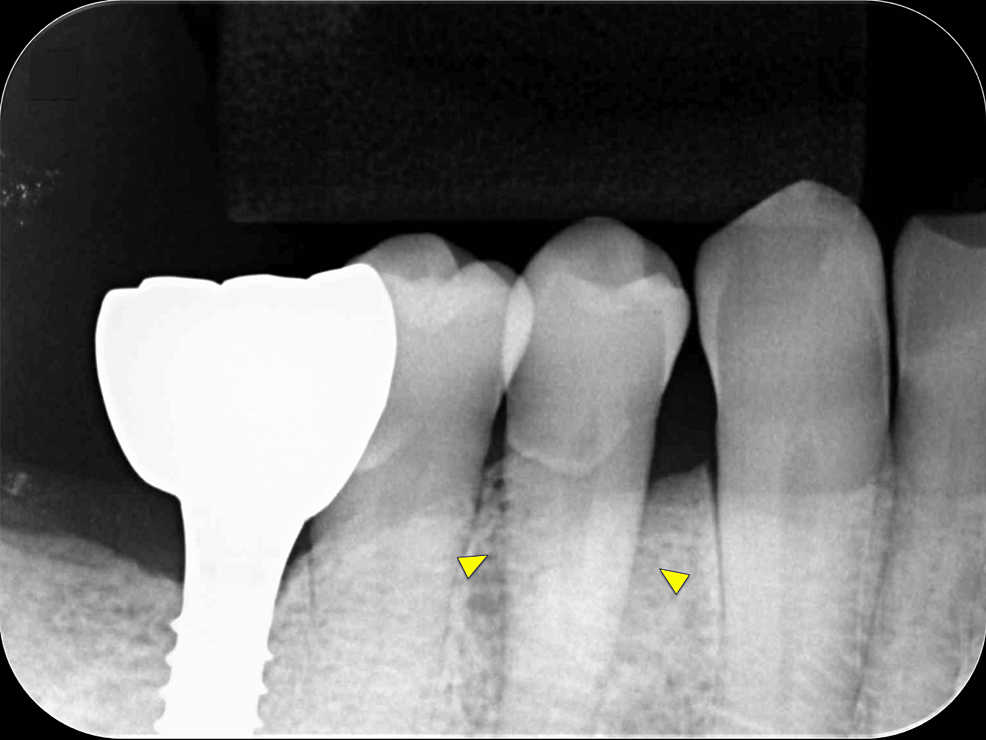

First, initial treatment including oral hygiene instruction was provided, followed by scaling and root planing. Teeth #16, #27, #37, and #46 were extracted, as they were considered too difficult to preserve. After reevaluation, a dental implant was provided for tooth #46. The patient was enrolled in supportive periodontal therapy after it was confirmed that the initial course of periodontal treatment had stabilized conditions. Subsequently, an acute periodontal abscess was observed in #44, however, requiring the start of anti-inflammatory treatment including periodontal pocket curettage under local anesthesia and oral antibiotics. Nevertheless, no improvement was found in the 6-mm buccal pocket of #44, so periodontal tissue regeneration therapy was planned. Before starting such treatment, in addition to intraoral radiography, cone-beam computed tomography (CBCT) was also performed using the 3DX Multi Image Micro CT (J MORITA Co., Ltd., Kyoto, Japan) (Figures 1, 2). The scan parameters were as follows: 90-kV tube voltage; 7-mA tube current; field of view, 60 mm x 60 mm; and slice thickness, 0.125 mm. The CBCT images revealed an intrabony, two-walled, defect around #44 that was slightly less radiolucent on the intraoral radiographic image. It was localized on the buccal side from the proximal to the distal aspect. A relatively large mandibular torus interior was also observed on the lingual side of #44 and #43.

Intraoral radiography and CBCT scanning were performed 14 months postoperatively (Figures 4, 5). The results were displayed on a personal computer monitor screen, and the morphology of the bone at the surgical site and its internal structure was observed in 3D, by which the regrowth of bone-like structures at the site of the intrabony defect was confirmed. At two years postoperatively, no subjective symptoms such as pain or objective signs such as tooth movement or gingival recession were observed. No other notable findings or abnormalities were observed, and the postoperative course was judged to be good.